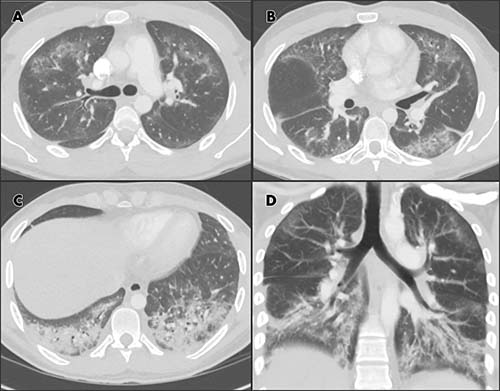

In one case highlighted in the report, Drs. Abbara and Kay illustrate some of the radiographic and CT findings of lung injury in the clinical case of a 24-year-old male patient with past medical history of asthma, who presented with shortness of breath, productive cough, chest pain and fever for one week. The patient reported current daily use of e-cigarettes (with tobacco) and marijuana, without substantial change in recent vaping habits. He had high white cell and platelet counts.

The radiologic findings included bilateral basilar predominant ground-glass and reticular opacities in both lungs. Histologic specimens obtained from the right lower lobe at biopsy were suggestive of lipoid pneumonia, according to the report. The patient was given steroids with a presumptive diagnosis of lung injury associated with e-cigarette use.

“The diagnosis of lung injury due to e-cigarette use should be a differential possibility in patients presenting with bilateral lung opacities on radiographs or ground-glass opacities on chest CT images and exposure to e-cigarette products within 90 days of the presentation,” Dr. Abbara said.